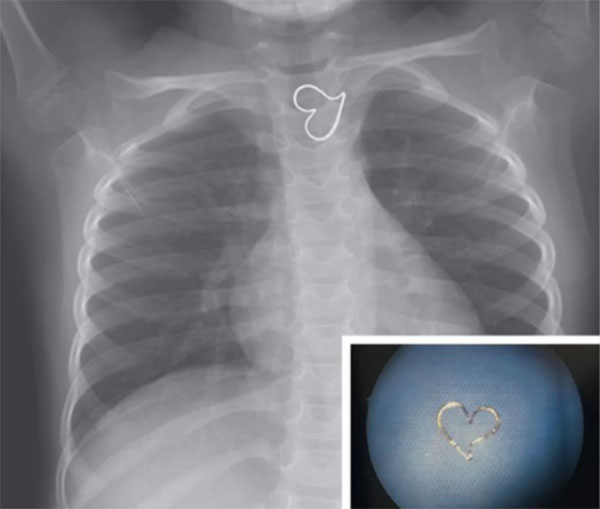

18/02/2019 16:10'Trái tim vàng' trên ảnh X-quang của bé gái

Theo Live Science, bức ảnh này được công bố mới đây trên tạp chí y học New England. Các bác sĩ tại Đại học California (Mỹ) cho biết bé gái ba tuổi được đưa vào phòng cấp cứu sau khi nuốt phải mặt dây chuyền màu vàng. Vì vậy, nhóm tác giả đặt tên ca bệnh là "trái tim vàng".

Qua ảnh chụp X-quang, đội ngũ y tế xác định dị vật hình trái tim mắc kẹt trong thực quản bệnh nhi. Do mặt dây chuyền nằm yên một chỗ, các bác sĩ nội soi lấy nó ra cơ thể cơ thể bé gái mà không cần phẫu thuật. Hiện bệnh nhi đã hồi phục và trở về nhà.